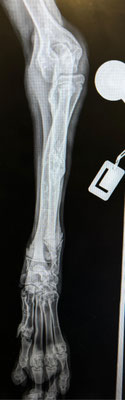

Im September 2025 haben wir Ihnen die kleine Finija vorgestellt: Gerade einmal vier Monate alt, wurde sie in einem erschütternden Zustand gefunden. Beide Hinterbeine waren gebrochen, eine Fortbewegung war für sie nur noch auf den Vorderpfoten möglich. Trotz starker Schmerzen zeigte Finija eine unglaubliche Willenskraft – ein kurzes Video aus…